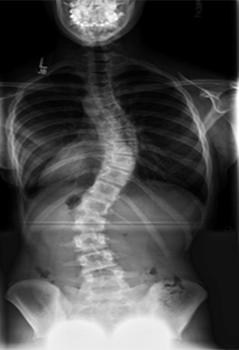

A 17 year old boy came to OPD with complains of progressive gait ataxia since last 2 years, spine deformity and urinary incontinence. On examination, he had ataxia, brisk knee reflexes, absent ankle jerks. The eye examination was normal. This was his Xray spine

- Which ataxia phenotype is this child fitting into

- What is the usual MRI finding in these cases

- Which vitamin supplementation should be tried in this phenotype